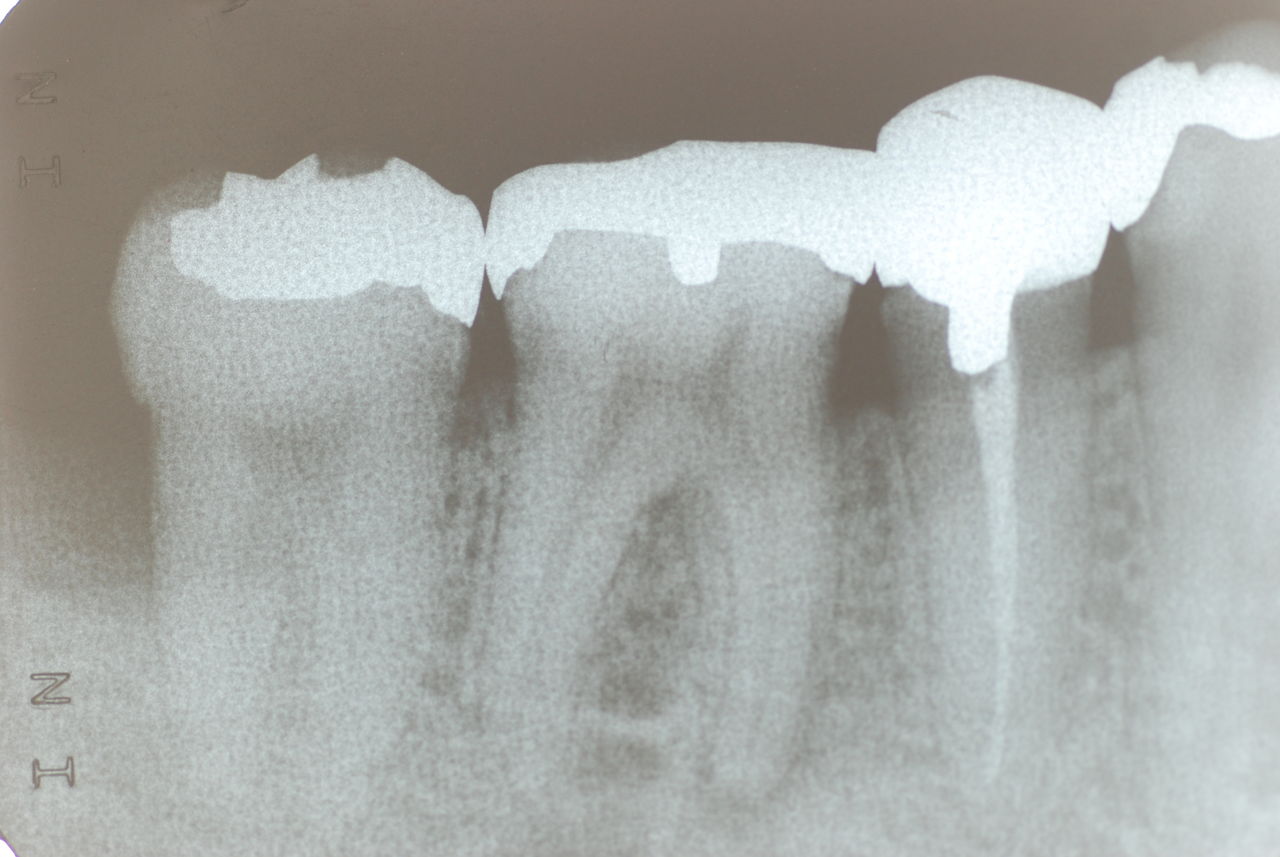

なかなかブラシの使い方ができていないようで、歯磨きと歯周病でのブラシの使い方は別なのですが、習ったことも検査もされずに金属を被せたりしているようで、これからも歯医者さんで抜かれたり、その後にインプラントのような高価な“クギ”を打ち込まれる方が増えるかと思うと残念です。

被せても、詰めても病気は治らないのですから。又病気の元になり易い不適合な差し歯や金属、インプラントがあればそこからバイキンが侵入して体に悪さもしやすいのではないかと心配しています。